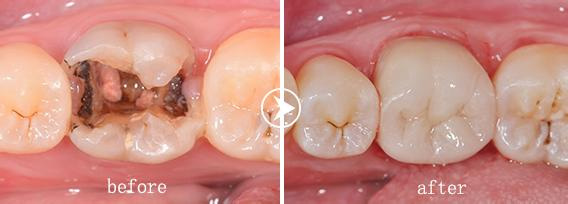

广州越秀圣贝口腔门诊部口腔您使用治疗系统治疗蛀牙

系统让整个治牙过程出血极少,几乎,不需麻醉,可用于蛀牙的根管治疗、牙周病治疗、人工种植牙、牙髓病及口腔软组织切除等方面,是目前口腔治疗的新,代表了口腔诊疗人性化、化和化的发展方向。